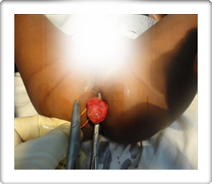

Rectal Polyp :-

It is mass or swelling arising from mucosal lining of bowel wall. It may be pedunculated or sessile. The polyp consists of rounded head and long pedicle which is attached to the mucosal surface. It my occur any where in the large intestine but most common site of polyp is recto sigmoidal region.

The polyp is delivered

at valium orifice and Kshar Sutra is ligated. The post operative review of 140 cases of rectal polyp treated by Kshar sutra did not show any recurrence during last 30 years review.